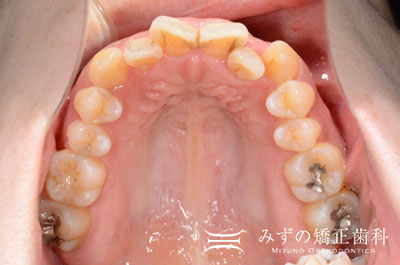

【症例2】見えにくい裏側矯正治療

- 治療前

- 治療後

- 治療名

- 見えにくい裏側矯正治療

- 患者様

- 26歳 女性

- 費用

- 1,386,000円(税込)

- 期間

- 24ヶ月(2年)

治療内容

-

患者様の症状

上顎の八重歯の歯並びが気になる。

治療法

矯正装置:上下裏側矯正装置、アンカースクリュー

抜歯:上顎左右小臼歯2本

上顎八重歯を解消するために、上顎左右小臼歯の抜歯を行い配列しました。 下顎は先天的に永久歯が2本不足していました。 -

治療結果

上下の正中も揃い、八重歯が解消しました。

適切な噛み合わせを与えることができました。

※治療結果は患者様によって個人差があります。

治療を行う上での 注意点 (リスク・副作用)

後戻り、治療への協力の必要性、審美観の個人差、歯根吸収